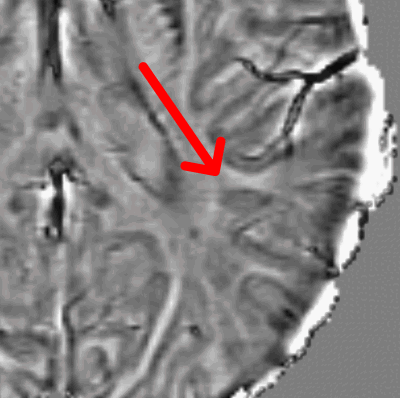

Paramagnetic (Iron) Rim Lesions

Multiple Sclerosis (MS) is characterized by the accumulation of areas of inflammatory injury ("lesions") to the brain and spinal cord. In the aftermath of a new lesion formation, the brain and immune system attempt to heal. In some cases — for reasons yet unknown — a lesion will fail to repair and instead develop ongoing, low-grade inflammation. In these types of "chronic active lesions", cells at the border (rim) of the lesion will often sequester iron, a paramagnetic molecule that can be readily visualized using special MRI sequences. These iron-laden cells tend to be highly inflammatory. They can be visualized as a dark border around a typical MS lesion. Many questions surround the role of these lesions in MS: what is the natural history of these lesions? Do they predict certain clinical outcomes? Can they be treated by any of our current therapies? We have recently shown that these lesions are highly specific for a diagnosis of MS. We collaborate closely with Daniel Reich at the NIH Translational Neuroradiology Section as well as with Sathish Dundamadappa at UMass Radiology and Alex Rauscher at University British Columbia.